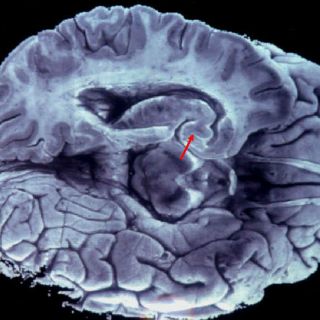

La administración del fármaco rebajó los niveles de tau en el cerebro de los ratones, ''rescatando los daños a la memoria y protegiendo contra la atrofia del hipocampo''.